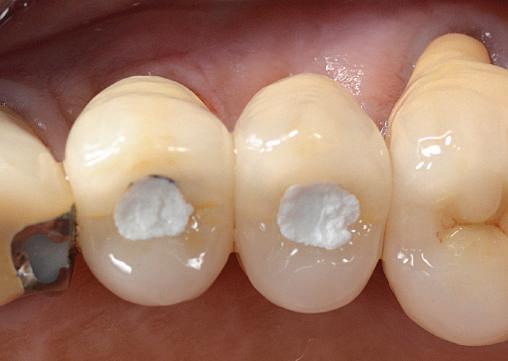

Datorită stabilității primare la inserare de aproximativ 35 Ncm pentru ambele implanturi, am optat pentru înșurubarea bonturilor intermediare conice Balance Base Narrow Straight GH 3.0 și vindecare transgingivală (fig. 2, 3). Inserarea acestor stâlpi s-a realizat la un cuplu de forțe de 25Ncm, cu ajutorul unei chei dinamometrice, aplicându-se ulterior cape de protecție (fig. 4). Vindecarea transgingivală postoperatorie a decurs fără complicații.

După aproximativ 10 săptămâni am hotărât protezarea preparațiilor 34 și 35 cu coroane metalo-ceamice și realizarea unei restaurări fixe metalo-ceramice înșurubate ocluzal la nivelul bonturilor intermediare de la implanturile 36 și 37.

Figurile 1. Status clinic şi radiologic iniţial; 2. Bontul Balance Base Narrow Straight GH 3.0; 3. Bonturile Balance Base Narrow aplicate imediat post-inserare la 25 Ncm; 4. Aplicarea capelor de protecţie şi sutura; 5. Stâlpii de amprentă înşurubaţi la nivelul bonturilor Balance Base Narrow;